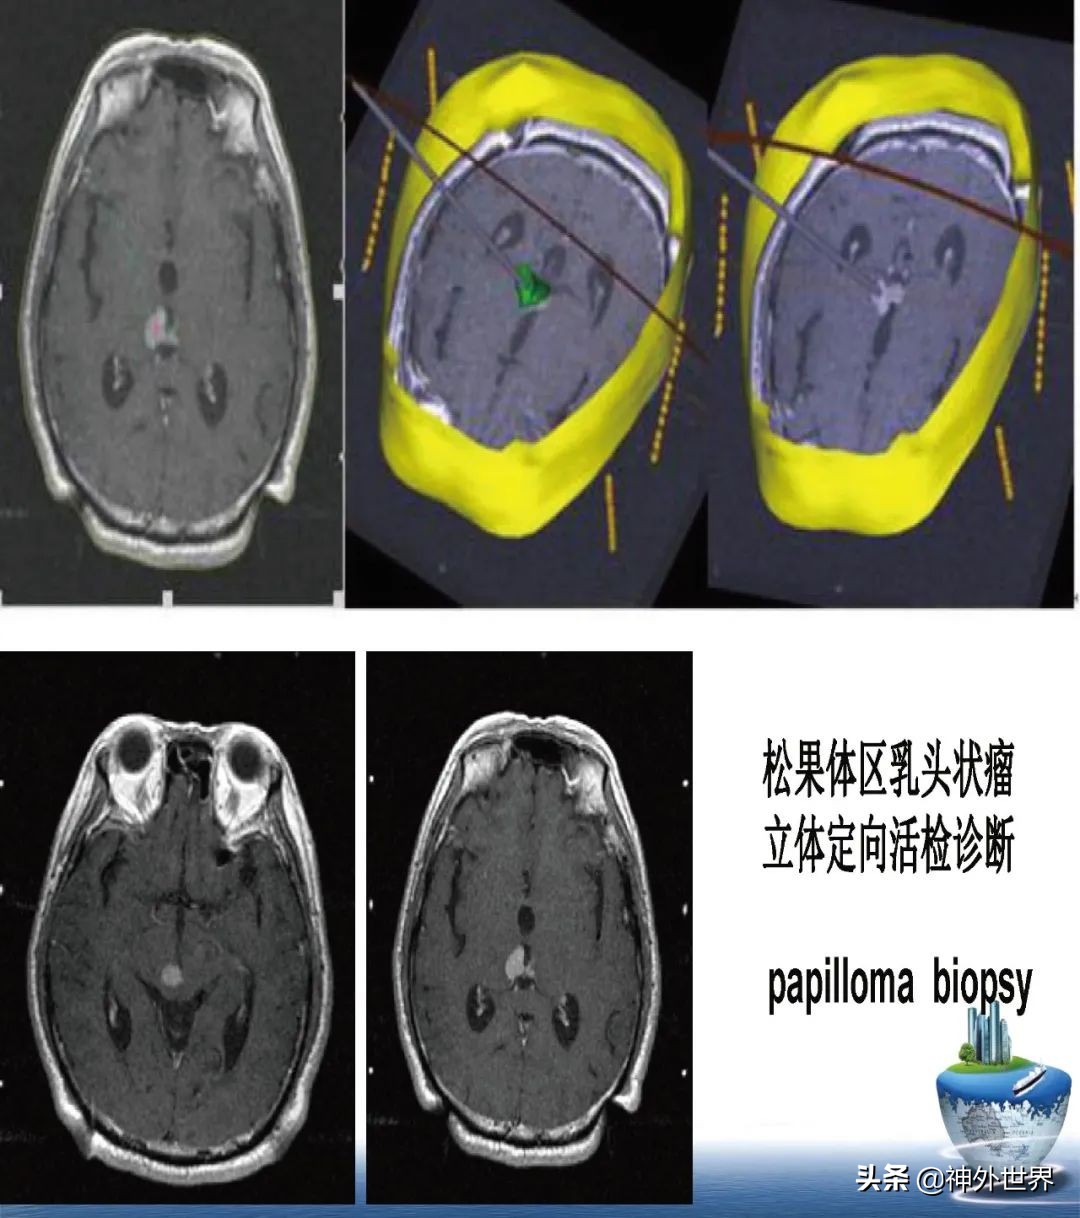

专业方向:颅内肿瘤的显微外科手术切除,颅咽管瘤综合治疗具有特色;在立体定向脑内病灶活检、立体定向清除脑干血肿、立体定向间质内放疗、机器人辅助神经外科手术方面具有专长。